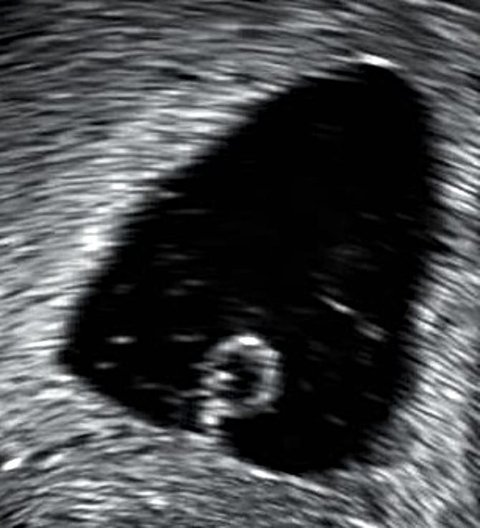

Ovum pregnancy symptoms. An ultrasound scan will be able to look at your uterus and will then be able to tell you whether or not an embryo sac is present or whether it is just the gestational sac. It s not able to turn into a viable pregnancy. Symptoms of blighted ovum. A blighted ovum is a term to explain an empty gestational sac explains octavia cannon d o an ob gyn with arboretum obstetrics gynecology in charlotte north carolina.

Causes in a normal pregnancy the egg starts dividing within hours after being fertilized. Most of the time the ovum gets destroyed during the first trimester. Mine lasted about 3 4 weeks from when i found out so the symptoms stopped at 12 weeks. A blighted ovum occurs when a fertilized egg implants in the uterus but doesn t develop into an embryo.

A blighted ovum eventually leads to miscarriage. A blighted ovum can occur very early in pregnancy before most women even know that they are pregnant. A pregnancy that results in a blighted ovum is also known as an anembryonic pregnancy and will ultimately end in a miscarriage sometimes before a woman even knows she is pregnant. The signs and symptoms of blighted ovum in the later pregnancy period is different from the ones in the early stages.